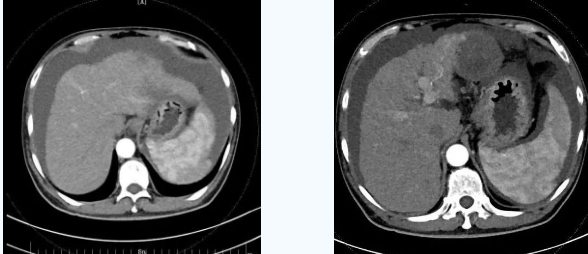

55歲的秦先生,于2021年10月被確診為肝癌晚期、慢性腎功能不全尿毒癥期,一直在口服靶向藥物進行治療,規(guī)律行腎透析治療。直至今年4月因肝癌破裂出血行肝動脈分支栓塞止血術(shù)后不久,秦先生開始出現(xiàn)了反復(fù)大量腹水,只能先暫停癌癥治療,解決腹水問題??墒乔叵壬奶幈疾▽めt(yī),腹水仍然沒有得到有效控制,于是在家人的多方咨詢打聽下,慕名來到西安國際醫(yī)學(xué)中心醫(yī)院。

入院后,消化內(nèi)科五病區(qū)韓國宏院長帶領(lǐng)團隊對患者做了深入的檢查,檢查后發(fā)現(xiàn)患者“肝硬化失代償期、頑固性腹水、原發(fā)性肝癌、慢性腎功能不全尿毒癥期、2型糖尿病、高血壓2級”等病癥,韓院長在對患者的病情進行反復(fù)評估分析后表示,首先要明確患者目前腎透析后,仍然是大量腹水、無尿,那么腹水是肝源性的還是腎源性的,遂請多學(xué)科會診,結(jié)合相關(guān)檢查后明確,秦先生目前的大量腹水是由于門脈高壓導(dǎo)致的頑固性腹水,只有先解決門脈高壓導(dǎo)致的頑固性腹水,才可以繼續(xù)進行癌癥治療,于是,韓院長決定為患者實施TIPS手術(shù)。

由于大量腹水、晚期肝癌加上尿毒癥等的綜合病癥,手術(shù)難度和危險系數(shù)都比平常增加了幾倍,面對這樣的情況,術(shù)前韓國宏院長帶著團隊反復(fù)分析討論,全面評估,在患者的各項指標達到手術(shù)標準后,對患者實施了經(jīng)頸靜脈肝內(nèi)門腔靜脈分流術(shù)(TIPS),手術(shù)取得成功,術(shù)后患者恢復(fù)良好。

術(shù)后一個月秦先生來院復(fù)查,腹水已明顯較前減少,精神和飲食較術(shù)前明顯好轉(zhuǎn)。